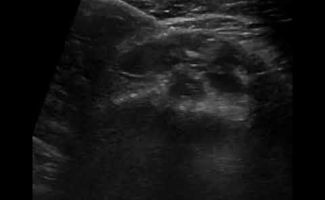

- Έγχυση Kορτικοστεροειδούς στο περίβλημα (έλυτρο) του τένοντα: Η έγχυση με κορτιζόνη καταστέλλει τη φλεγμονή γύρω από τον τένοντα, οδηγώντας στην άμεση ανακούφιση του ασθενούς από το πόνο και το πρήξιμο. Η στοχευμένη διενέργεια αυτών των ενέσεων είναι πολύ σημαντική: η έγχυση πρέπει να γίνει στο περίβλημα του τένοντα, και όχι στο εσωτερικό του, καθώς η έγχυση στο εσωτερικό μπορεί να προκαλέσει φθορά και ρήξη του τένοντα. Τα μηχανήματα υπερήχων μας παρέχουν το απαραίτητο επίπεδο ακρίβειας καθώς καθοδηγούμε τη βελόνα με ταυτόχρονη απεικόνιση και διοχετεύουμε το φάρμακο εκεί ακριβώς που χρειάζεται. Επομένως, το επίπεδο ακρίβειας που εγγυάται η απεικόνιση σημαίνει ότι υπάρχει υψηλή πιθανότητα η θεραπεία να είναι ακόμα πιο αποτελεσματική.

- Απόλυτη Ακρίβεια: Οι υπέρηχοι επιτρέπουν στους Ιατρούς-Ακτινολόγους να εντοπίζουν με ακρίβεια τον φλεγμονώδη τένοντα και να οπτικοποιούν τη θέση της βελόνας κατά τη διάρκεια της ενέσεως. Αυτή η στοχευμένη προσέγγιση εξασφαλίζει την τοποθέτηση της ένεσης με ακρίβεια στην περιοχή που πλήττεται, βελτιώνοντας την αποτελεσματικότητά της.

- Ασφαλείς: Σε σύγκριση με την ενέσιμη θεραπεία χωρίς υπερηχογραφική καθοδήγηση (τυφλή ένεση), η εικόνα πραγματικού χρόνου επιτρέπει στον ιατρό να διεξάγει την ένεση ακριβώς στο σημείο που χρειάζεται, αποφεύγοντας επικίνδυνες περιοχές όπως τα νεύρα και τα αγγεία.